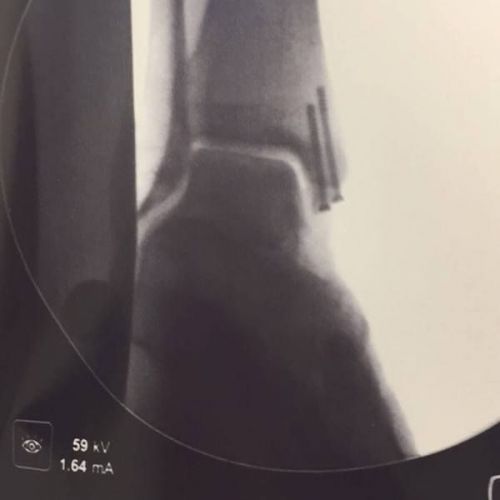

E’ stato lo stesso 27enne originario della Val di Susa ad annunciarlo sulla sua pagina Facebook: “Pensavo di finire la carriera senza viti 🙄😜 dopo l'infortunio di St. Moritz la mia caviglia non è mai guarita quindi oggi sono stato operato dal Prof. Niek Van Dijk presso l'Hospital Santa Maria a Porto. (Portogallo) #johnnymalleolo#avvitato#niekvandijk”. Ignoti i tempi di recupero.